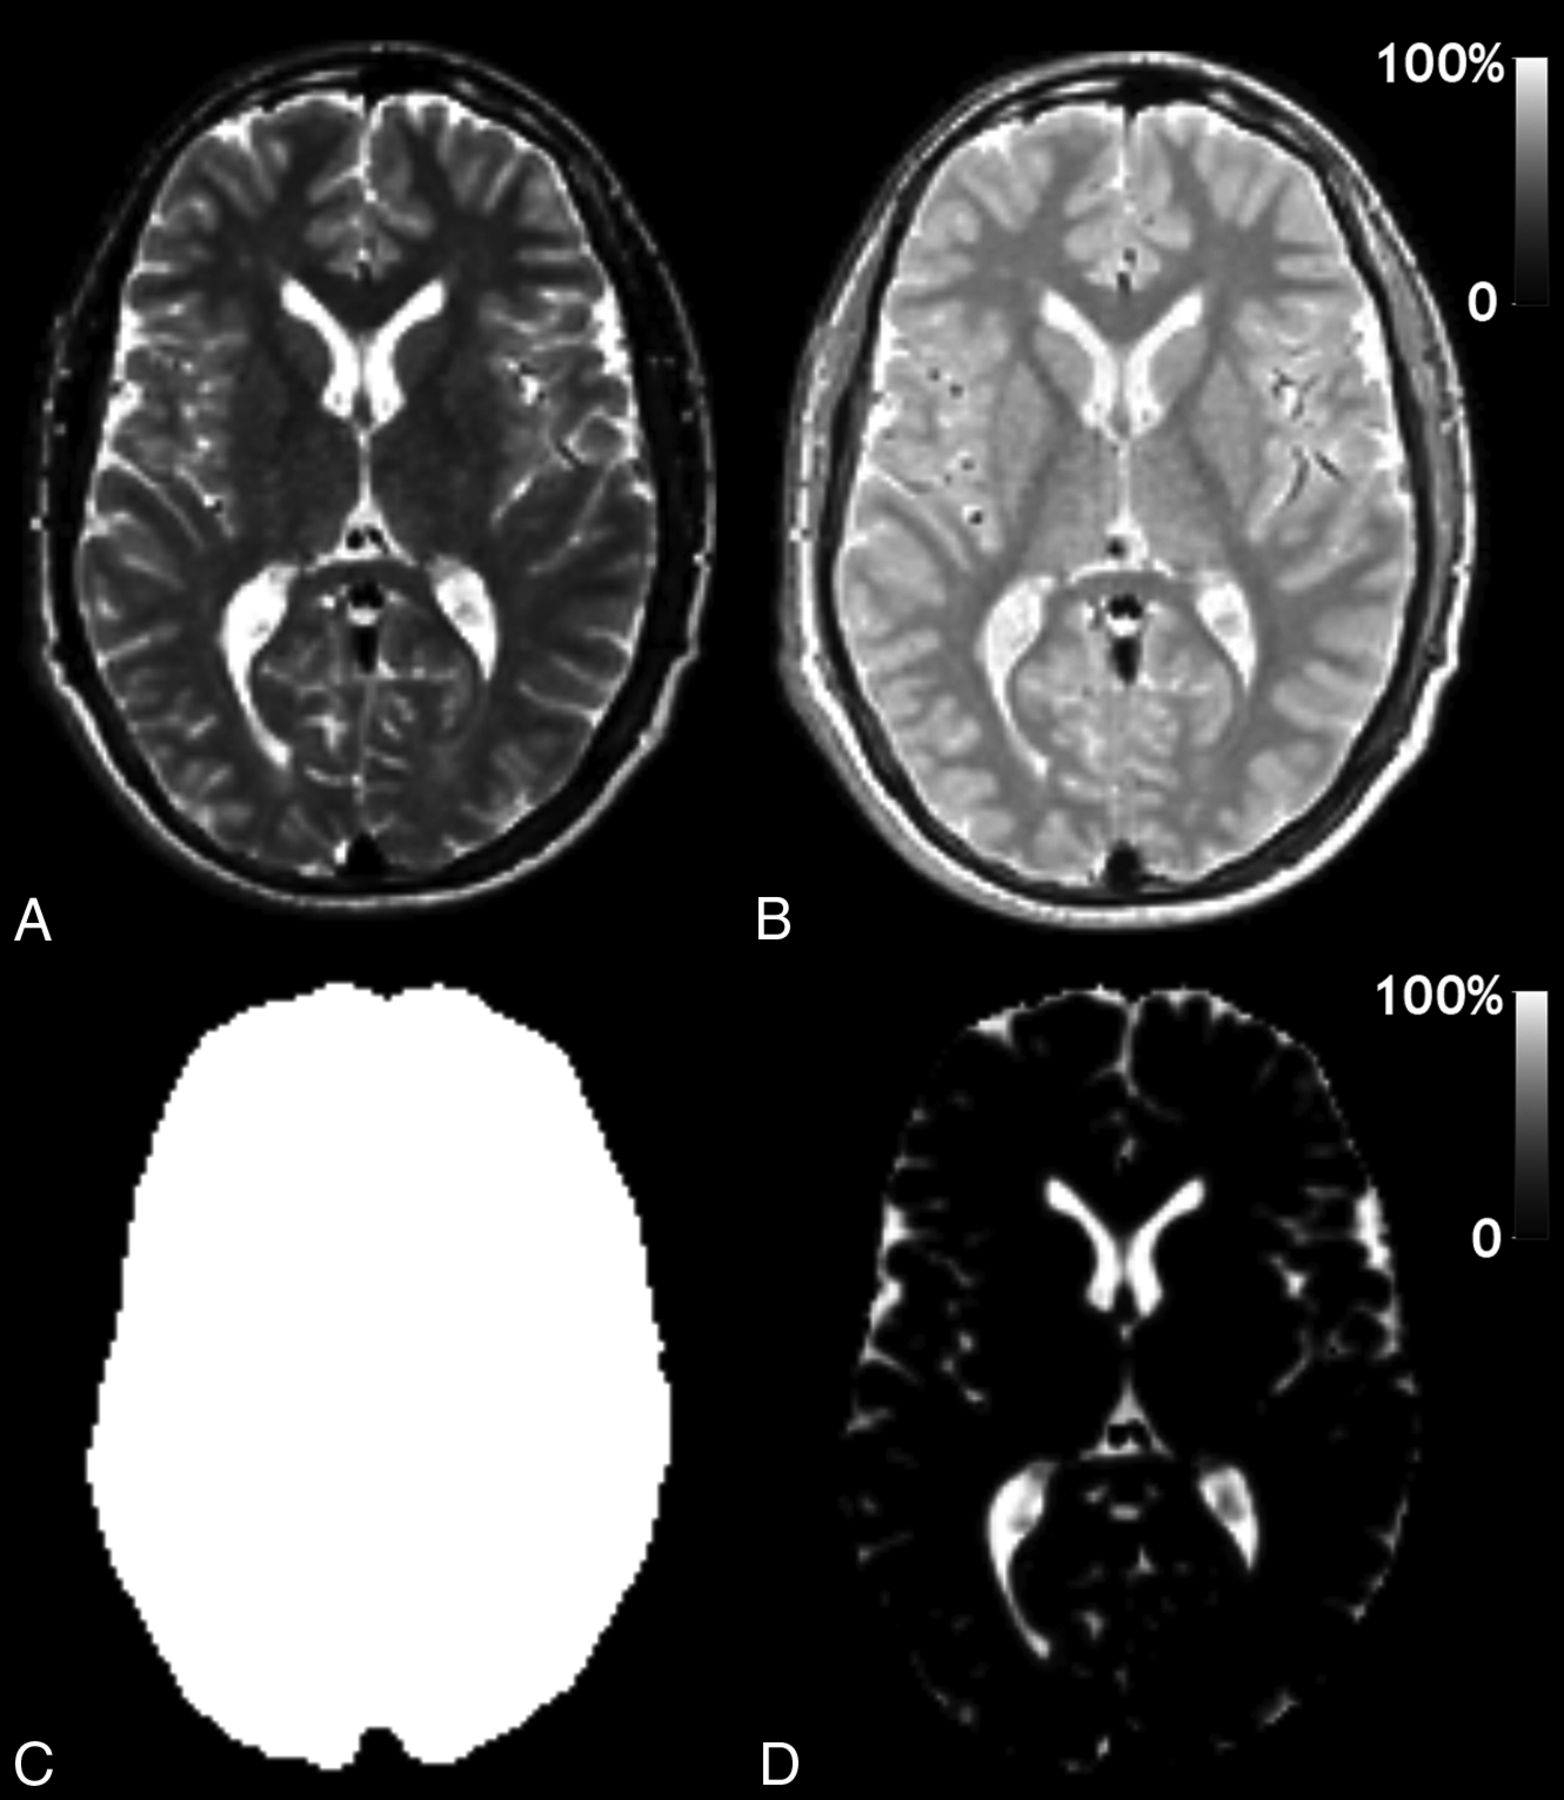

The calculation of the intracranial volume (ICV), the brain parenchymal volume (BPV), and brain parenchymal fraction (BPF = BPV / ICV) is an automatic function of SyMRI 9.0. The same software also shows the R1, R2, and PD maps of the entire acquisition volume. Typical images and maps from this software in our patients are shown in Fig 1. An adjustment was made in the software to extract the average R1, R2, and PD values for the entire brain and gray and white matter. This was done by taking the ICV and removing all CSF (clipped at 50% partial volume) and subsequently eroding 1 pixel on all sides of the volume to remove the partial volume effects of CSF. The available GM and WM segmentation maps were used to retrieve the average R1, R2, and PD of GM and WM inside the eroded volume.

Typical output of the SyMRI software: A, Synthetic T2-weighted image of a section of the brain of one of the patients. This synthetic image was generated from the R1, R2, and PD maps in combination with a TE/TR = 100/4500 ms. B, PD map on a scale of 0%–100%, in which 100% corresponds to pure water at 37°C. C, Automatically generated intracranial mask (ICV). D, Automatically generated CSF partial volume map on a scale of 0%–100%. The brain parenchymal volume is calculated as the sum of all ICV minus the sum of all CSF. The brain parenchymal fraction is calculated as BPV/ICV.